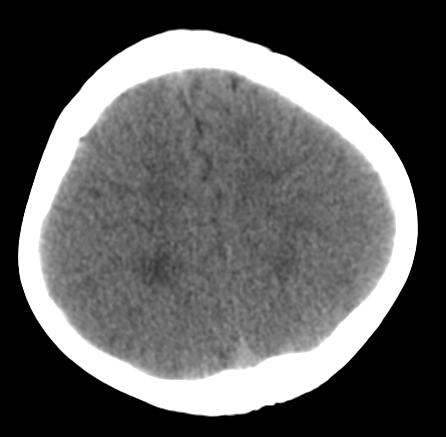

女,3岁,头部外伤一小时。半卵圆中心低密度是什么意思,病灶?侧脑室?请指教。

正常表现

幼儿正常脑白质表现,长期观察,必要时mr

不是侧脑室,考虑正常脑白质。为慎重,建议mr!